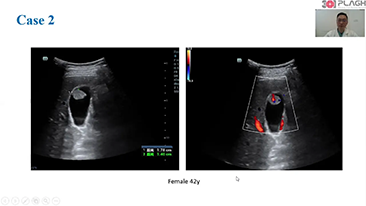

How Clearly Can You See a Liver?

Ultrasound contrast imaging plays a significant role in identifying focal liver lesions, such as hemangioma or liver cancer.

Ultra-wide non-linear UWN+ contrast imaging technology provides better penetration, higher contrast-tissue ratio, with lower MI and longer perfusion time observation.